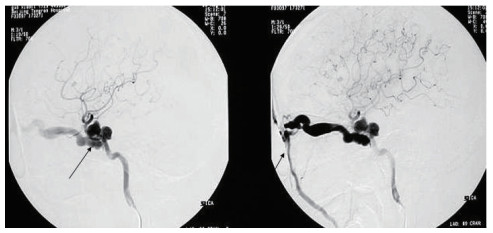

患者入院后行全脑血管造影明确诊断,见图 3。结果显示118例(81.82%)瘘口位置位于颈内动脉C4-C5段,26例(18.06%)位于C3-C4段。引流方向135例(94.75%)向眼上静脉、岩下窦引流。确诊CCF后患者行Matas试验,后在颈内动脉海绵窦瘘栓塞术中,瘘口未见进一步扩大,海绵窦无进一步扩张。144例患者中可脱球囊是最常用的栓塞材料[9],占120例(83.88%),弹簧圈9例(6.25%),弹簧圈+Onyx胶12例(8.33%),Willis覆膜支架3例(2.08%)。

| 图 3 黑色箭头显示了异常增粗的眼静脉 Fig 3 Black arrows show abnormally thickened ocular veins |